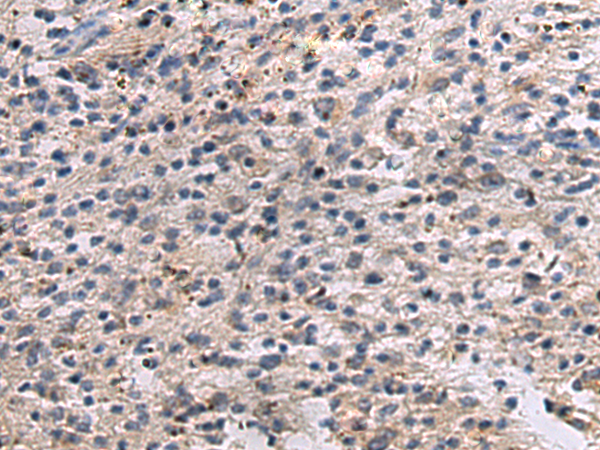

IHC positive control: |

Human brain and Human esophagus cancer |

IHC Recommend dilution: |

50-100 |